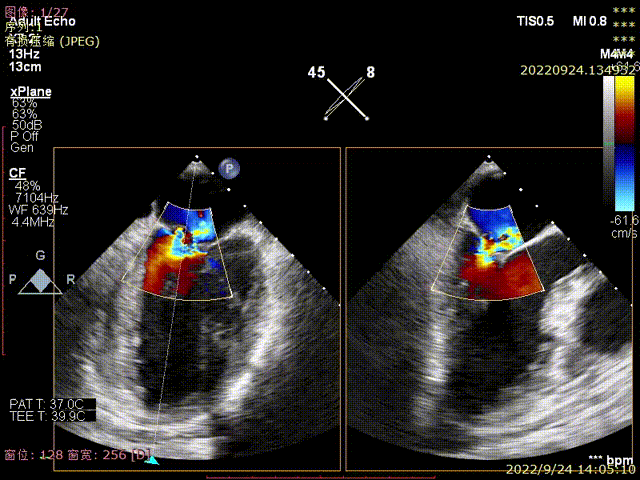

图1-2,术前心超显示大量偏心性二尖瓣反流(反流位置位于P3近PC位置)